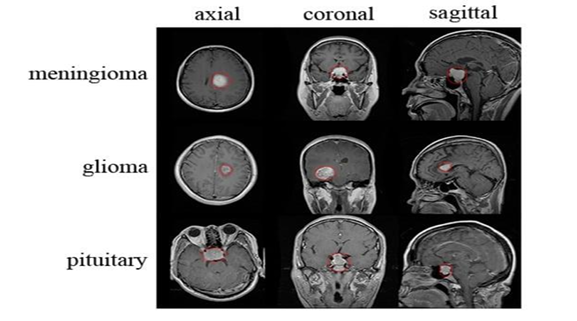

The brain, a highly complex organ with approximately 100 billion neurons and 1,000 trillion synapses, is prone to life-threatening conditions like brain tumors, caused by abnormal cell growth. In India, 28,000 cases of brain tumors are reported annually, with an alarming 86% mortality rate. Similarly, the United States anticipates 18,990 deaths from brain and CNS tumors in 2023. Brain tumors can be benign or malignant, originating either as primary tumors in the brain or secondary tumors spread from other organs. Common types include meningiomas, gliomas, and pituitary tumors, each posing severe risks due to increased intracranial pressure.

We used the publicly available Brain Tumor Detection and Classification MRI image Kaggle dataset are (https://www.kaggle.com/datasets/sartajbhuvaji/brain-tumor-classification-mri). There are 3264 brain MRI images in dataset which have been labelled as glioma tumor, meningioma tumor, no tumor and pituitary tumor. Including the number of these brain MRI images are 926 images of glioma, 937 images of meningioma, 500 images of no tumor and 901 images of pituitary tumor. The images were processed, they were divided into a training and validation set using an 80%-20% split respectively. Depending on their types and grades, brain tumor can vary in terms of size, location and shape.